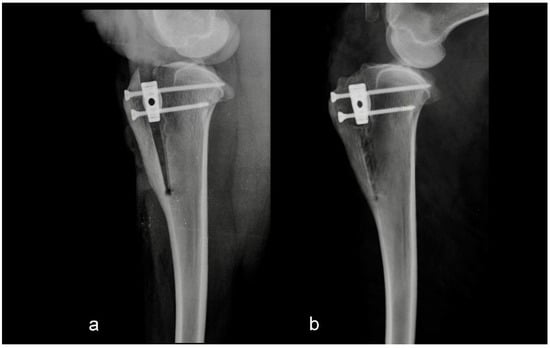

The second group consisted of five sheep in which the intraoperative or postoperative discrepancies from preoperative planning were found. Discrepancies were either the osteotomy line was too close to the tibial crest, or the tibial crest was cracked at the level of the Maquet hole (Figure 2 and Figure 3).

Figure 2. Mediolateral radiograph of the stifle in Group 2 immediately postoperatively (a) and at six months postoperatively (b). The tibial crest was cracked at the level of the Maquet hole.